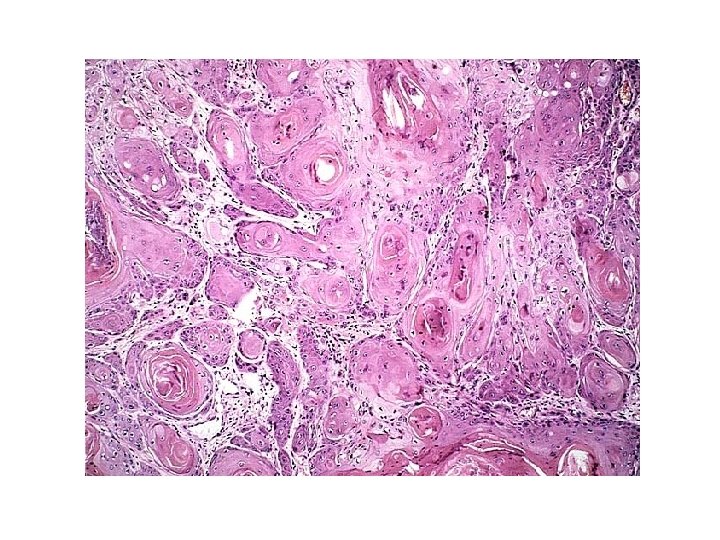

NEOPLASMS OF THE PENIS • SQUAMOUS CELL CARCINOMA (SCC) – EPIDEMIOLOGY • UNCOMMON – LESS THAN 1 % OF CA IN US MEN • UNCIRCUMCISED MEN BETWEEN 40 AND 70 – PATHOGENESIS • POOR HYGIENE, SMEGMA, SMOKING • HUMAN PAPILLOMA VIRUS (16 AND 18) • CIS FIRST, THEN PROGRESSION TO INVASIVE SQUAMOUS CELL CARCINOMA

Squamous Cell Carcinoma

SCC OF THE PENIS • Clinical course – Usually indolent – Locally invasive – Has spread to inguinal lymph nodes in 25% of cases at presentation – Distant mets rare – 5 yr survival • 70% without ln mets • 27% with ln mets